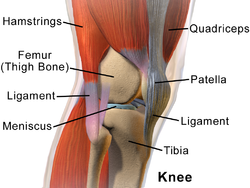

The knee is one of the most important joints of our body. It plays an essential role in movement related to carrying the body weight in horizontal (running and walking) and vertical (jumps) directions.

The knee is a hinge type joint that connects the thighbone (femur) and the shinbone (tibia). Ligaments (lateral collateral, medial collateral, anterior cruciate and posterior cruciate) are tissues that connect the two bones and allow the knee to bend, straighten and rotate. Articular cartilage covers the ends of the bones and under the kneecap (patella) to assist in movement. The meniscus is a cushion of cartilage between the leg bones which helps to absorb shock.